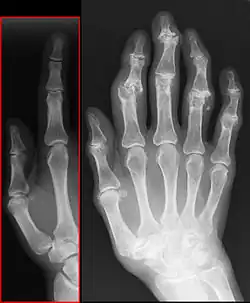

(1) (Rand-)Osteophyt

(2) subchondrale Sklerosierung

(3) Geröllzyste

(4) Gelenkspaltverschmälerung

Der Patient berichtet bei der Anamnese über Gelenkschmerzen, anschließend muss geklärt werden, bei welchen Gelegenheiten dieser Schmerz auftritt. Es folgt die klinische Untersuchung der Gelenkkontur, der Funktion, der Bandstabilität, der umgebenden Muskulatur. Dann schließt sich, je nach Erfordernis, eine bildgebende Diagnostik an, wie beispielsweise Röntgen, Computertomographie (CT) oder Magnetresonanztomographie (MRT). Zeichen einer bestehenden Arthrose sind dabei eine Verschmälerung des Gelenkspaltes, Sklerose (eine reaktive Knochenverdichtung zu beiden Seiten des Gelenkspaltes), Osteophytenbildung an den Gelenkrändern und subchondrale Zystenbildungen des gelenkbildenden Knochens, die durch feine Rissbildungen des Knorpels und Durchtritt von Gelenkflüssigkeit in die darunter liegende Knochenschicht entstehen. Eine Verschmälerung des Gelenkspalts deutet dabei auf eine Arthritis oder eine Arthrose hin, je nachdem, ob der gelenknahe Knochen verdünnt oder verdickt ist.[17]